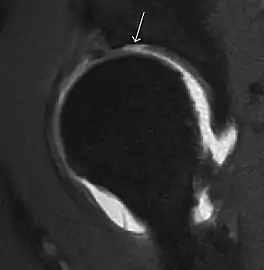

Most of the angles and measurements described in the plain radiograph section can be accurately reproduced on MRI. In addition, the superiority of MRI resolution with intra-articular contrast allows detection of labral and chondral abnormalities that may influence the choice of medical, percutaneous, or surgical management (Figure 9).[1]

Figure 9:

Sagittal T1 weighted image showing anterosuperior labral tear.[1]

Sagittal T1 weighted image showing chondral lesion.[1]

MR arthrography has proven superior in accuracy when compared to native MR imaging. It is considered the best technique to assess the labrum. Knowledge of the normal variable morphology of the labrum helps to differentiate tears from normal variants. A triangular shape is most commonly seen in 66% of asymptomatic volunteers, but round, flattened, and absent labra can also be found in asymptomatic populations. MR arthrography has demonstrated sensitivity over 90% and specificity close to 100% in detecting labral tears. Loose bodies are demonstrated as filling defects surrounded by the hyperintense gadolinium.[1]

Association between labral tears and chondral damage has been demonstrated. This underscores the interaction between cartilage and labrum damage in the progression of osteoarthritis. Chondral damage to the posteroinferior part of the acetabulum as a contrecoup lesion occurs in approximately one-third of pincer cases secondary to persistent abutment on the anterior part of the joint leading to a slight posteroinferior subluxation. This is considered a bad prognosis sign.[1]

MR arthrography can also demonstrate ligamentum teres rupture or capsular laxity, which are debated causes of microinstability of the hip. Elongation of the capsule or injury to the iliofemoral ligament or labrum may be secondary to microtrauma in athletes. MR can demonstrate abnormalities in these cases, such as increased joint volume or a ligamentum teres tear (Figure 9).[1]